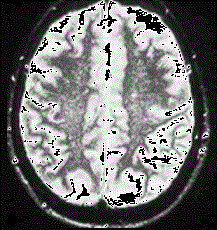

问题 根据MRI表现考虑为何种疾病是 ( )

选项 A、亚急性硬化性全脑炎 B、进行性风疹全脑炎 C、皮质一纹状体-脊髓变性 D、进行性多灶性白质脑病 E、羊瘙痒病

答案 C